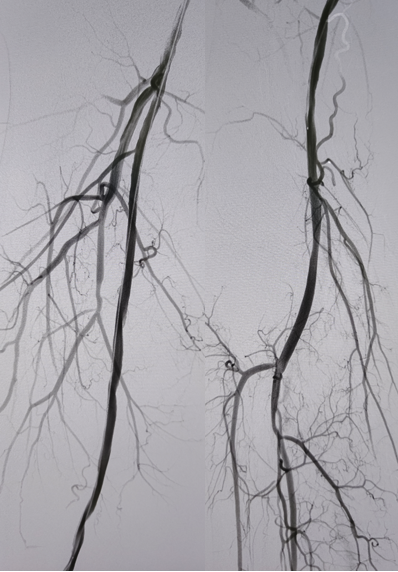

病例2(股腘动脉长段闭塞):

另一例长段闭塞病变,IVUS证实导丝真腔通过后,指导术者选择了合适尺寸的Rotarex导管进行减容,联合普通球囊(POBA)预扩及DCB治疗,获得了满意的管腔,避免了支架植入。

图:一期支架植入